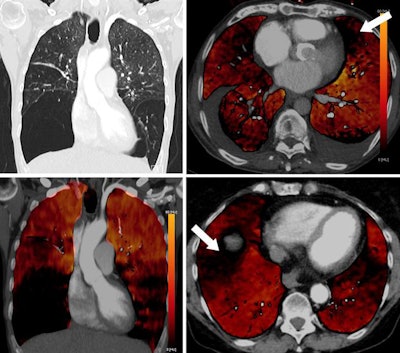

Blood clots that do not lead to a total vessel obstruction are not necessarily associated with a perfusion defect on PBV images (see figure below). On the other hand, completely obstructing blood clots normally lead to corresponding perfusion defects.

PBV images of a 46-year-old woman with right-sided emboli. Coronal PBV image (top left) shows clot in the anterior lower lobe artery (arrow) with total lumen obstruction and PBV defect (asterisk). Coronal (bottom left) and axial (top and bottom right) PBV images of the same patient show a nonobstructing clot in the posterior lower lobe artery (rounded arrows) without associated PBV defect. Asterisks in the right images indicate PBV defect due to obstructing clot shown in top left image. All images courtesy of Dr. Aleksander Kosmala.Dual-energy CT scans involve the acquisition of two datasets at low and high kilovoltages, as follows: